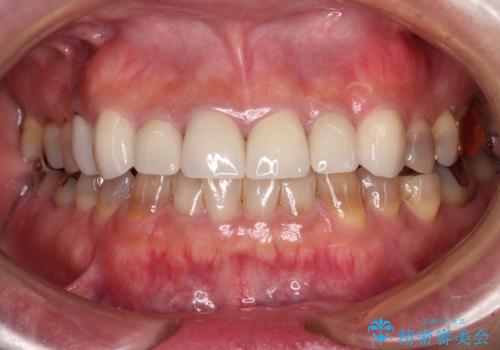

- 前歯のテトラサイクリンによる変色歯と、レジン充填の色の違いを気にして来院された患者様です。

患者様の希望により、前歯6歯をオールセラミッククラウンにて補綴することとしました。

長年前歯の色の違いに悩んでいらっしゃったようですが、仮歯に変えた時点で統一感のある白さとなり喜んで頂きました。

わずか1ヶ月の間にとても自然な仕上がりのセラミッククラウンが装着され、患者様には大変満足していただきました。